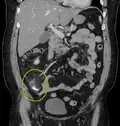

A fecalith marked by the arrow which has resulted in acute appendicitis.

A fecalith is a stone made of feces. It is a hardening of feces into lumps of varying size and may occur anywhere in the intestinal tract but is typically found in the colon. It is also called appendicolith when it occurs in the appendix and is sometimes concurrent with appendicitis.[1] They can also obstruct diverticula. It can form secondary to fecal impaction. A fecaloma is a more severe form of fecal impaction, and a hardened fecaloma may be considered a giant fecalith. The term is from the Greek líthos=stone.[2]

A small fecalith is one cause of both appendicitis and acute diverticulitis.